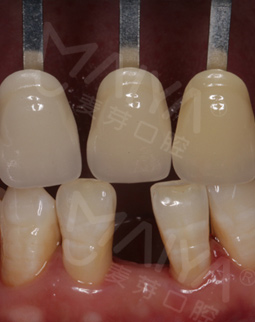

手术当天,我先和在场的朋友们分享了我的缺牙感受,然后进了手术室,除了麻醉的时候有点感觉外,种牙没有一点痛感,自己小咪了几分钟牙就种好了,而且出血量微乎其微,专家们技术真的非常高超。看着镜子里面的牙齿,发现跟周围的真牙完美的融合了,一点也看不出假牙的样子,特别美观舒服。回到现场,大家问我种牙什么感觉,我最想说的就是:种牙真的不疼,而且整个手术时间很快,要相信我们的医生和技术。